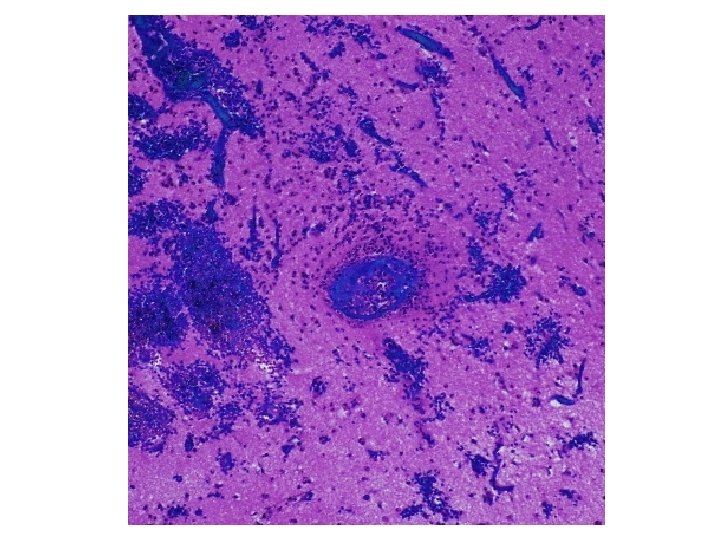

CD 3 CD 68 LCA

173 involved vessels 88 in grey matter, 85 in white matter Mean diameter 66. 7 ± 3. 9µm Mean ratio of wall thickness to diameter is 0. 18 ± 0. 01 Vessels < 100µm are venules/veins or arterioles/small arteries But ratio is ca. 0. 1 for venous vessels, ca. 0. 5 for arterial, so most are venous

Diagnosis • Acute vasculitis, mostly venous, in association with ulcerative colitis • Predominantly neutrophilic (acute) • Venous involvement explains the extensive hemorrhage since tissue is under arterial perfusion pressure